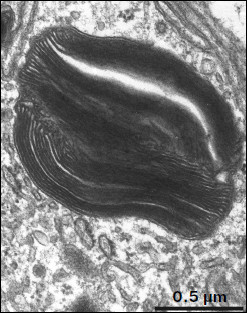

Fig. 2. Phagosome ultrastructure at high magnification. Layers of photoreceptor membranes are clearly seen.

Ultrastructure of pigment epithelium cells. Pigment epithelium of Wistar cells (Fig. 1) consists of a layer of cells in the apical part of which there are fine strands of vertical extended cytoplasm offshoots surrounding rod outer segments. Phagosomes, debris of photoreceptor outer segments that underwent phagocytosis by pigment epithelium, sometimes can be seen in these cytoplasm offshoots near rod cell bases (Fig. 2). The characteristic ultrastructural feature of pigment epithelium is the presence in apical part of the cytoplasm of a layer of electron-dense structures (Fig. 1). As a rule, these structures are considered in the literature to be lipofuscin granules [12, 13]. We found in the apical part of pigment epithelium cells of 11-month-old Wistar rats practically continuous homogeneous layer of electron-dense structures – cytoplasmic inclusions (Fig. 1). Ultrastructural analysis of this layer showed that it contains morphologically extremely heterogeneous structures. First of all, these are lipofuscin granules. On the electron-microscopic photograph of the pigment epithelium region (Fig. 3a) arrows point to ultrastructure of two lipofuscin granules in the case of different section direction. It is seen that ultrastructure of lipofuscin granules corresponds to classical concepts. They can have round, oval, or polygonal shape depending on the section plane. Each granule is surrounded by a single-layer membrane contains moderately contrasting amorphous stroma substance (arrow 1) and aggregates of osmiophilic small granules (arrow 2). Oval osmiophobic regions or spherules (arrow 3) restricted by a layer of smallest particles of high electron density (arrow 4) can be seen within the amorphous substance. Besides, this layer of electron-dense structures includes large formations of variable size, shape, and internal arrangement. Figure 3b shows different structure of these formations. They are restricted by a single-layer membrane (arrow 1), contain granular stroma substance of different density in separate granules (for comparison arrows 2 and 3 point to granules of different density), and have heterogeneous ultrastructure along their length. Thus, arrow 4 in Fig. 3b points to a granule containing a region of fibrillar structure (arrow 5) as well as the close-type layers of concentric membranes restricting the space filled by the granular substance of electron density lower than that of stroma (arrow 6). We suppose that different ultrastructure of these formations is due to the fact that they are mutually transient structures, because various transient stages can be detected in their internal arrangement.

Figure 1

Fig. 1. Pigment epithelium region of 11-month-old Wistar rats. Arrows: 1) phagosomes; 2) the layer of electron-dense cytoplasmic inclusions; 3) mitochondria; N, cell nucleus.